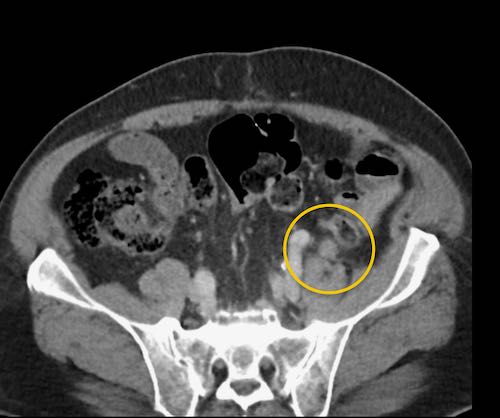

Cuộn xem ảnh CT

Ca lâm sàng 1

Cuộn qua các lát cắt.

Bạn có thể phát hiện tất cả các tổn thương cấy ghép phúc mạc không?

Bệnh nhân này đã được phẫu thuật và toàn bộ phúc mạc được ghi nhận phủ kín bởi các tổn thương u dạng kê.